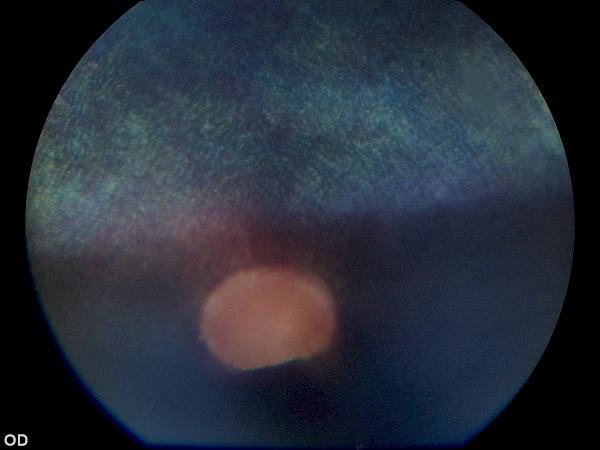

angeborene Netzhautablösung, ein geeigneter Kandidat für eine erfolgreiche Netzhautoperation angeborene Netzhautablösung, ein geeigneter Kandidat für eine erfolgreiche Netzhautoperation

vor Operation vor Operation